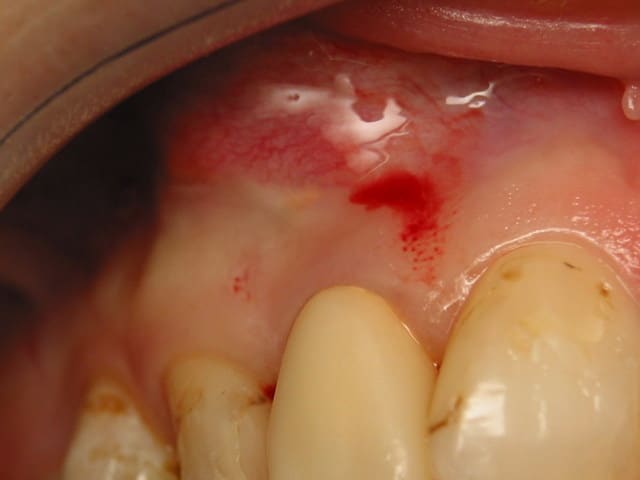

18/11/2005 à 00h43

une semaine apres, la cicatrisation est en bonne voie. J'ai une solidification du caillot. la gencive a presque completement cicatrisee et j ai un exudas jaune tres clair qui sort par un ou deux petits trous situes le long de la cicatrice. C'est normal a J+8 d'autant que les tetracyclines que j'ai melangées au bioos acidifient le milieu. Toujours sous antibio. La patiente n'a pas eu mal et a gonflé pendant 2 jours.

photo : pas d ecarteurs c trop tot encore. Notez la propreté des fils a propylene en 6/0